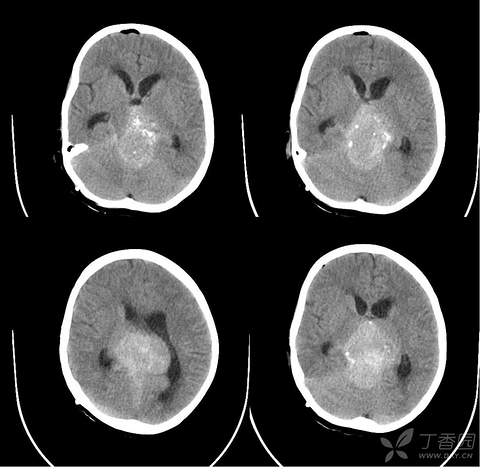

月经没来,恶心、呕吐,验孕棒显示“两条杠”,却不是怀孕

原来没怀孕,验孕棒也有可能两条杠,还有早孕反应。难怪怀孕早期除了验血还要做B超。转自妇产科垚哥。 19岁大学生,单身,月经没来,恶心、呕吐,验孕棒显示“两条杠”。妈妈对她说:怎么学会说谎了?医生说:她还是很乖的,只是脑里有个肿瘤。